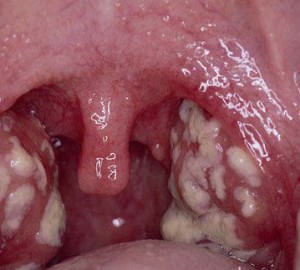

Этот тип ангины проявляется наличием налета и образованием язв на миндалинах. Как показано на изображении, при данном заболевании поверхность миндалин покрывается бело-желтыми пятнами налета. При удалении пленки механическим путем обнажается неглубокая язвочка.

Рекомендация: При стоматической ангине редко наблюдается поражение только миндалин, обычно язвы появляются также на других участках – небе, слизистой щек и т.д.